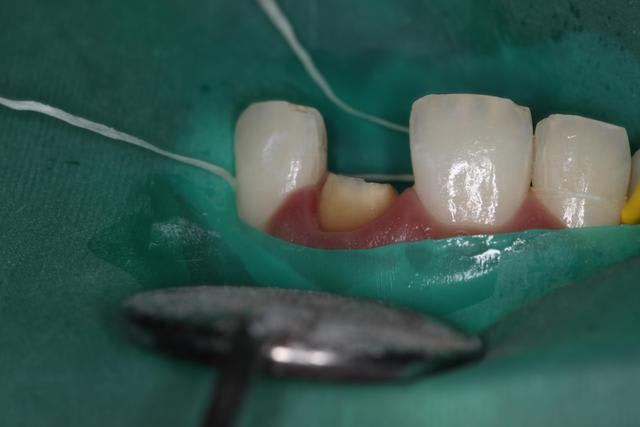

Jour d'essayage : le prothésiste m'a fait les 2 possibilités Emax et Zircone :)

Emax = trop translucide / parait trop gris encore. Teinte correspondant pourtant. Souci de grade d'opacité ?

Zircone mieux : je pense par contre que c'est bien l'armature zircone qui fait toute l'opacité.

Pas assez "jaune" au collet, et manque de translucidité sur les bords proximaux.